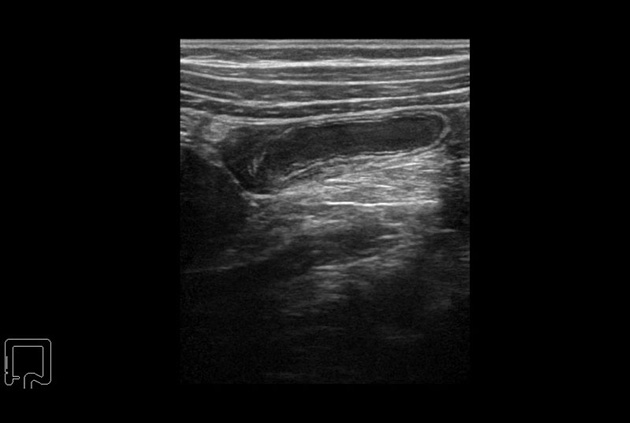

Trapezoidal Scan

Use of trapezoid mode with the linear transducer extends the width of the field of view permitting a greater understanding of the orientation and size of the target and its surroundings.